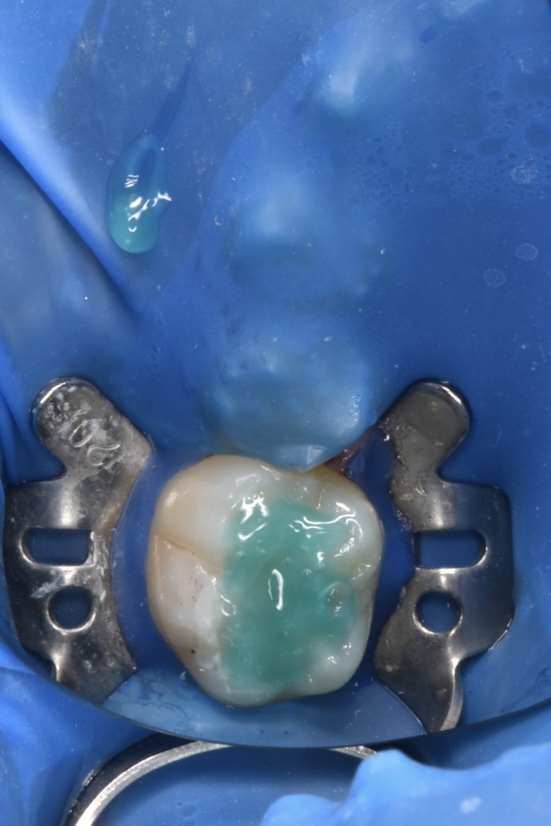

治療プロセス(自由診療のみ適応しているものもあります)

- ラバーダムをするため治療中水がお口の中に入ってこないので楽